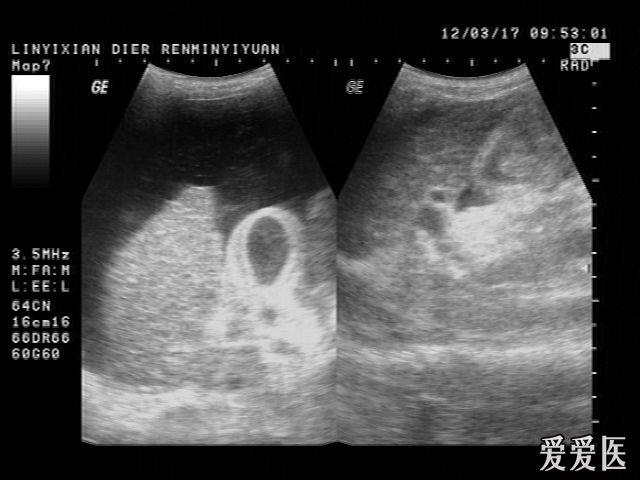

超然精彩病例欣赏之——急性胆囊炎并胆囊结石,胆泥团形成

胆囊壁呈双边征改变,并可见宽基底占位性病变

胆囊炎的超声特点是双边征(因为炎症导致胆囊壁水肿所致),胆囊壁增厚

胆囊体积增大,囊壁增厚呈"双边影". 2.囊内可见细密光点或斑片状回声.

3. 双边征

4cm,常有双边征.对提示胆囊炎有较大价值.